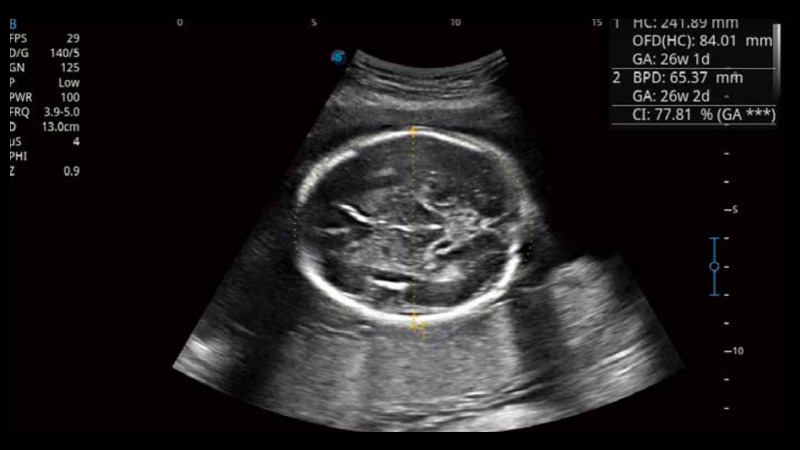

S-Fetus基于大數(shù)據(jù)深度學(xué)習(xí)算法,能夠幫助您在產(chǎn)前篩查過(guò)程中智能識(shí)別胎兒標(biāo)準(zhǔn)切面、自動(dòng)測(cè)量并錄入報(bào)告。一個(gè)按鍵,即可智能、精準(zhǔn)、高效地獲取胎兒生理指標(biāo),極大簡(jiǎn)化您的產(chǎn)科檢查操作。

可快速對(duì)產(chǎn)科掃查切面完成胎兒生理學(xué)參數(shù)的自動(dòng)測(cè)量,減少操作者按鍵次數(shù),大幅提升檢查效率。